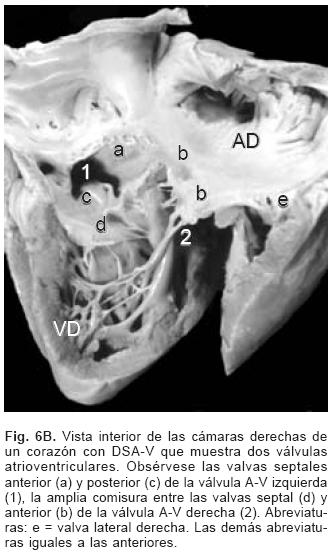

De los sesenta y cinco corazones con válvula común en veinticinco se determinaron los tipos de la clasificación de Rastelli que fueron los siguientes: en once (44%) las valvas anterosuperiores derecha e izquierda se insertaron a través de sus cuerdas tendinosas sobre la cresta del tabique ventricular y la CIV se ubicó en los espacios intercordales (tipo A de Rastelli) (Figs. 1A y 5A). En un espécimen las valvas anterosu–periores izquierda (valva puente) y derecha se insertaron sobre la cara derecha del tabique ventricular por debajo de su cresta (Fig. 5B) y en otro dicha inserción se hizo en la parte superior del cuerpo de la trabécula septomarginal (Fig. 5C). En ocho corazones (32%) la inserción de esas valvas se estableció en un músculo papilar situado en la unión del tabique ventricular con la pared libre del ventrículo derecho y la valva anterosuperior izquierda pasó como puente por encima de la CIV (tipo B de Rastelli) (Figs. 1B y 5D) y en seis corazones (24%) la inserción de las valvas anterosuperior izquierda (valva puente) y derecha se insertaron en un músculo papilar de la pared libre del ventrículo derecho y esta valva se ubicó por encima de la CIV (tipo C de Rastelli) (Figs. 1C y 5E). En los cuarenta corazones restantes no fue posible determinar los tipos de Rastelli debido a que treinta y tres de ellos presentaron doble entrada ventricular (Fig. 6A) dos tuvieron modificaciones anatómicas generadas por la cirugía y cinco por presentar mutilaciones realizadas durante la necropsia. Los cinco especímenes con dos válvulas separadas tuvieron estructura trifoliada dentro de la unión A–V común (Figs. 3B y 6B); la válvula A–V izquierda mostró una valva lateral y dos septales anterior y posterior unidas a la cresta del tabique ventricular, lo que obliteró la CIV (Fig. 6C). La válvula A–V derecha mostró una valva septal displásica, una anterior y una posterior (Figs. 3B y 6B).

La anatomía básica de los 2 tipos de DSA–V fue la misma. Todos presentaron anillo fibroso A–V común, reducción de la distancia A–V–ápex e incremento de la distancia ápex –válvula aórtica, el tabique ventricular estuvo excavado (Figs. 4 y 6C), el anillo fibroso mostró dilatación anteroposterior, desencuñamiento aórtico, alteración en el esqueleto fibroso del corazón consistente en un anillo fibroso A–V común, ausencia del septum membranoso y persistencia de la continuidad entre la válvula aórtica y la válvula A–V común o válvula A–V izquierda (Fig. 6D), desviación anterior del tracto de salida del ventrículo izquierdo (Figs. 4 y 6C) y en dos especímenes obstrucción de éste por inserción en su interior de la valva anterosuperior izquierda (Fig. 7A). En un espécimen con una válvula A–V común se desarrolló una banda anómala de miocardio entre la pared libre y el tabique ventricular, lo que separó el componente derecho de la válvula A–V común en dos orificios valvulares (Fig. 7B). Las alteraciones asociadas se consignan en la Tabla III.

Se ha postulado que el defecto septal A–V es consecuencia de la falta de desarrollo y fusión de las almohadillas endocárdicas A–V dorsal y ventral, proceso anómalo que explica todas las alteraciones anatómicas presentes en esta cardiopatía.1,21 En vez de formarse dos anillos fibrosos como ocurre en el corazón normal se constituye uno común, dentro de él se forman dos válvulas A–V separadas o una válvula A–V común, lo que ha servido de base para la clasificación de esta cardiopatía congénita.2–4 Ambas formas tienen las mismas características patológicas básicas. Las dos válvulas separadas son de estructura trifoliada, la izquierda presenta 2 valvas septales anterior y posterior y una lateral, las valvas septales están separadas por una comisura que en el pasado se consideró erróneamente como una hendidura que según su extensión puede provocar insuficiencia valvular.23 Este concepto surgió debido a que la válvula A–V izquierda de esta cardiopatía se consideró homóloga de la válvula mitral del corazón normal, en realidad ambas son análogas, es decir cumplen una función similar pero tienen orígenes diferentes; ya se mencionó que en el corazón normal la valva medial de la válvula mitral deriva preponderantemente del componente izquierdo del tabique A–V doblado mientras que en esta cardiopatía la válvula A–V izquierda se origina de un nivel más inferior a partir del mesénquima que circunda el canal A–V común. En rigor en esta cardiopatía la válvula A–V izquierda no debe llamarse mitral, ya que su constitución es trifoliada, por lo que es preferible denominarla válvula A–V izquierda; las valvas septales de ésta se unen de manera continua a la cresta del tabique ventricular, con lo que queda obliterada la CIV perimembranosa y de entrada. Este hecho es determinante del establecimiento del cortocircuito por encima de las valvas A–V; el espacio entre éstas y el borde inferior del tabique interatrial comúnmente se ha considerado como FP, que en realidad es la suma del DSA–V y del FP; cuando éste está presente el borde inferior del tabique interatrial es cóncavo y queda por encima del plano del anillo fibroso A–V. Se han descrito casos en que dicho borde inferior no es cóncavo sino recto y coincide con el plano A–V, situación en la que está ausente el FP y el cortocircuito interatrial se establece a nivel del defecto septal A–V.2,9 Cuando se desarrolla una válvula A–V común con su patrón de cinco valvas, la gran comunicación permanece permeable.1,2,16,21